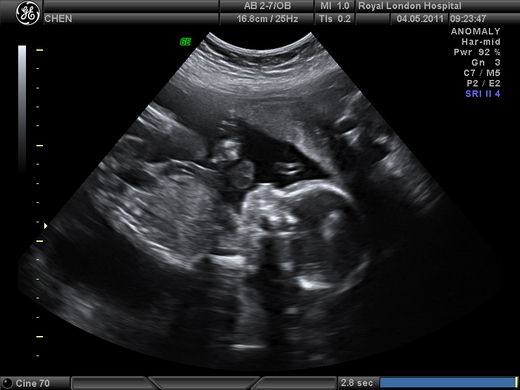

滿十二週的第一次超音波,只確認肚子裡真的有個小人,一切發展正常,還看不出性別. 我們興沖沖的拿著超音波照片回家,左看右看覺得這個翹著腳躺在媽媽肚子裡的小寶好可愛. 好奇心使然,我迫不及待想知道小寶是男生還是女生,小包倒是偏好傳統路線,想等小孩出生的那一刻才被告知. 拗不過老婆的意思和爸媽的關切,小包只好同意提前開獎,不過再怎麼早,也只有等到滿二十週,回台灣照高層次超音波時才會知道. 這段時間裡,我總在尋找徵兆,猜肚子裡是男孩還是女孩.

好不容易等到在台灣照超音波那一天,我打算等醫生都檢查得差不多再開口問性別. 醫生在肚子上塗上潤滑劑,超音波機在肚皮上推了幾下,第一句話就是: "是女生喔!" 我和小包沒想到問都沒問,醫生開門見山就開獎,錯愕又驚喜的微笑著互看一眼. 接下來我只記得醫生逐一檢查各部位,胎兒生長正常,手腳十指健全,但是腦子裡完全被粉紅色的喜悅占據,沒辦法認真的聽醫生的各項說明.

走出診間,小包忙著用i-phone把超音波照片傳給法國的包爸包媽,告訴他們包家終於有女孩了.